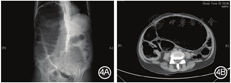

该病术前较难诊断,容易误诊为成人先天性巨结肠。Dingemann和Puri [3]对11篇幼儿神经节细胞缺乏症文献进行荟萃分析时发现,该病与先天性巨结肠在临床表现上无明显差异。此外,有报道指出,神经节细胞缺乏症相对发病年龄更大,且女性比例高[4]。术中可以发现明显的狭窄段,狭窄段主要位于降结肠或乙状结肠,病变肠段内神经节细胞数量的明显低于正常,近端肠段明显扩张呈巨结肠样改变,见图3。手术方式采用和特发性巨结肠一致的结直肠次全切除术,将扩张的近端肠段和狭窄的远端肠段一并切除,该类患者直肠较少受累,故行回肠直肠吻合或者升结肠直肠吻合。